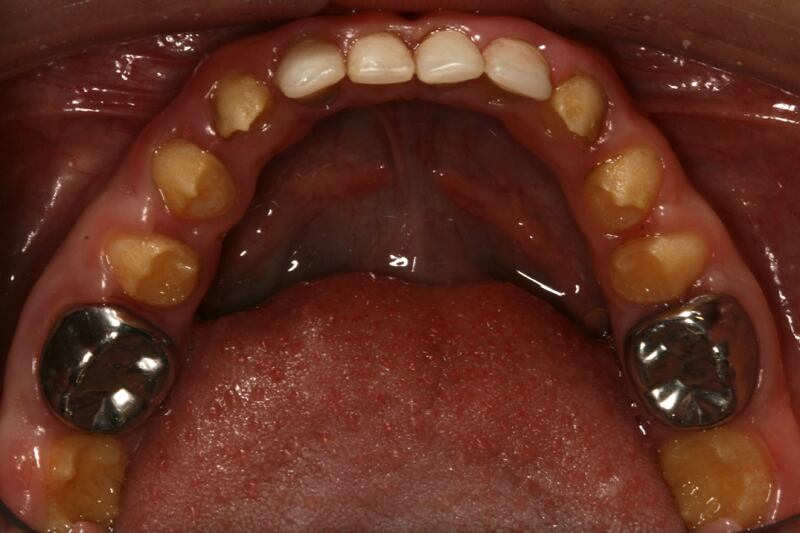

Este padecimiento, llamado amelogénesis imperfecta, se caracteriza porque el esmalte de los dientes es mucho más delgado y débil, por lo que la sensibilidad a la hora de morder, masticar o lavarse los dientes, es mucho mayor y causa fuerte dolor. Esto ocurre tanto con los dientes de leche como con los permanentes.

Además, al tener poco esmalte, los dientes se ven amarillos, lo que también afecta la salud emocional de los pacientes.